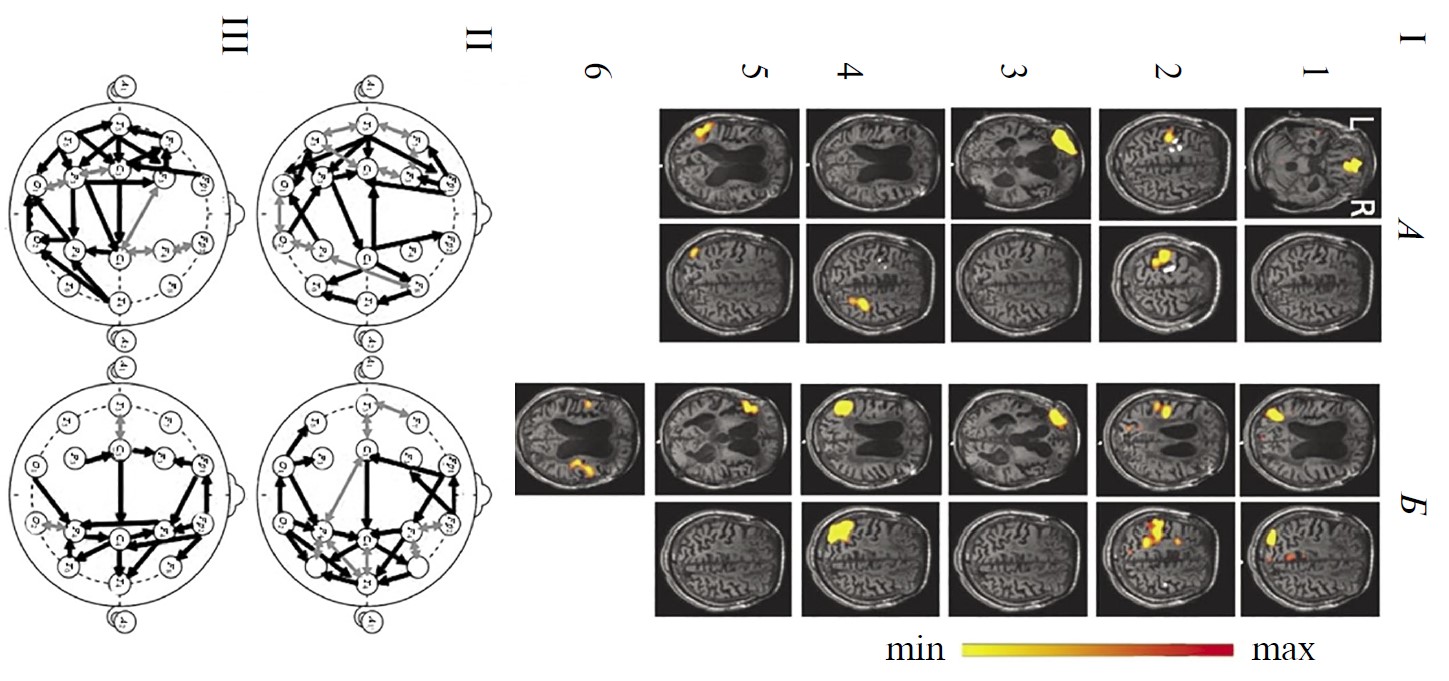

Рис. 1. Функциональные сети функциональной магнитно-резонансной томографии (фМРТ) и коннективность ЭЭГ-диапазона 1–15 Гц у здоровых испытуемых в состоянии покоя (n = 15).

А — усредненные по группе испытуемых RSN фМРТ: 1 – DMN, 2 - сенсомоторная, 3 – сеть управляющих функций (исполнительного контроля), 4 – лобно-теменная, 5 – слуховая, 6 – речевая. Шкала справа характеризует уровень максимальной интенсивности сети. Б, В — усредненная в этой же группе испытуемых коннективность ЭЭГ по корреляции Пирсона. Черные линии — однонаправленные связи, серые — двунаправленные, согласно методу причинности Грейнджера. Б — коннективности, рассчитанные на непрерывных записях, В — в режиме псевдо-ВП. Г — зоны концентрации функциональных связей ЭЭГ: а — лобные, б — височно-передневисочные, в — центральные, г — затылочно-теменные.

На рис. 1 представлены также результаты групповой оценки коннективности ЭЭГ диапазона 1–15 Гц этих испытуемых: при непрерывной записи состояния покоя (рис. 1, Б) и в режиме псевдо-ВП (рис. 1, В). На обеих схемах видно значительное число внутри- и особенно межполушарных связей, превышающих уровень корреляции Пирсона 0.5. Многие из них являются разнонаправленными (согласно методу причинности Грейнджера). Важно подчеркнуть, что паттерны связей характеризуются выраженным сходством друг с другом при обоих методах расчета коннективности. Хотя число отобранных связей несущественно меньше при расчете в режиме псевдо-ВП: 33 и 29 соответственно. Особенностью непрерывных записей ЭЭГ является также более частая встречаемость (на 7) двунаправленных связей.

Общее количество коннективностей ЭЭГ преобладает в передних корковых областях. В характере внутриполушарных связей, в первую очередь для непрерывных реализаций ЭЭГ (рис. 1, Б), можно отметить преимущественную правостороннюю направленность (по Грэйджеру) и превалирование их числа в правом полушарии, что, согласно литературным данным может рассматриваться как отражение возможно большей сопряженности этой гемисферы с ощущением своего тела [53] и самоосознанием [54].

Выделить на рис. 1 на схемах Б и В локусы топографического соответствия отдельным сетям фМРТ покоя затруднительно. Однако можно отметить несколько корковых областей, характеризующихся концентрацией функциональных связей: симметричные лобные, центральные, затылочно-теменные, а также височно-передневисочные. Топография этих локусов коннективности ЭЭГ (рис. 1, Г) совпадает с активными зонами сразу нескольких сетей фМРТ покоя: DMN, сенсомоторной, управляющих функций, слуховой и речевой. Можно полагать, что указанные области концентрации связей ЭЭГ можно рассматривать в качестве зон межсетевой коннективности, наличие которой отмечено в ряде публикаций в качестве значимой для восстановления сознания [43, 55].